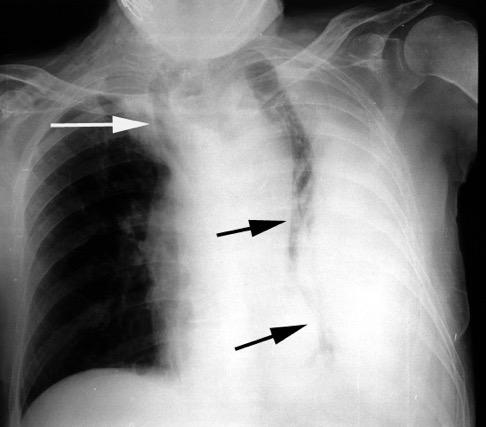

El aire penetra en inspiración en el espacio pleural. No sale en espiración. Desplazamiento importante de mediastino y silueta cardiovascular.

Atropellado. Neumotórax bilateral.

TC: contusión pulmonar severa. Enfisema subcutáneo. Signo del surco profundo

Visible en radiografías en decúbito supino de los pacientes con neumotórax por la acumulación de aire en el seno costofrénico.

“Deep sulcus sign”. Seno costofrénico aumentado en anchura y profundidad

Polireddy K et al. Blunt thoracic trauma: role of chest radiography and comparison with CT findings and literature review . Emerg Radiol 2022.

Kumaresh A et al. Back to Basics – ‘Must Know’ Classical Signs in Thoracic Radiology. Thoracic Radiology. J Clin Imaging Sci 2015.